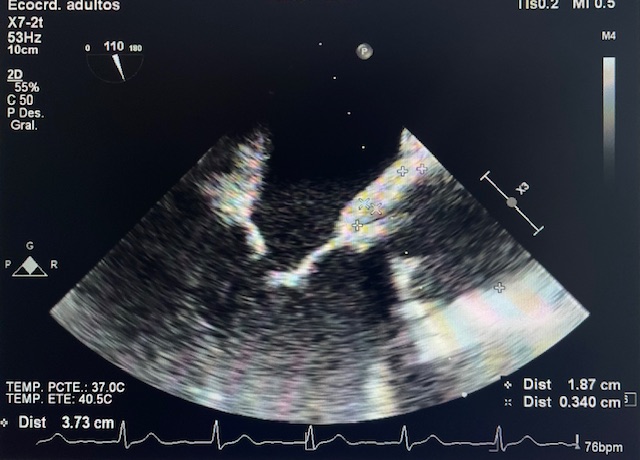

Antecedentes personales: HTA, dislipemia, carcinoma de cavum en tratamiento activo, TVP bilateral, estenosis aórtica por válvula bicúspide (RVAo por bioprótesis 2016), endocarditis protésica por L. rhamnosus con recambio valvular en diciembre 2023.

Ingreso del paciente en Medicina Interna con meropenem + daptomicina:

Ingreso posterior en UCI para estabilización previa a recambio valvular, cambiando su antibiótico a penicilina + gentamicina + daptomicina.